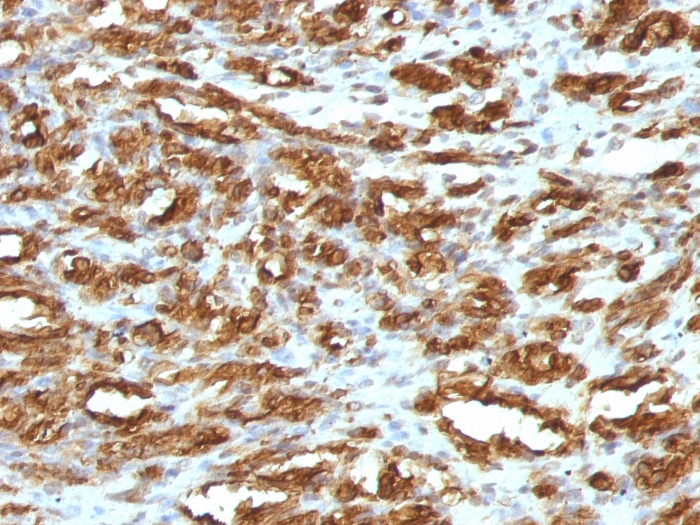

Formalin-fixed, paraffin-embedded human Leiomyosarcoma stained with Muscle Specific Actin Mouse Monoclonal Antibody (HHF35).

This antibody recognizes actin of skeletal, cardiac, and smooth muscle cells. It is not reactive with other mesenchymal cells except for myoepithelium. Actin can be resolved on the basis of its isoelectric points into three distinctive components: alpha, beta, and gamma in order of increasing isoelectric point. Anti-muscle specific actin recognizes alpha and gamma isotypes of all muscle groups. Non-muscle cells such as vascular endothelial cells and connective tissues are non-reactive. Also, neoplastic cells of non-muscle-derived tissue such as carcinomas, melanomas, and lymphomas are negative.It stains tumors of smooth muscle (leiomyomas and leiomyosarcomas) as well as skeletal muscle (rhabdomyomas and rhabdomyosarcomas).